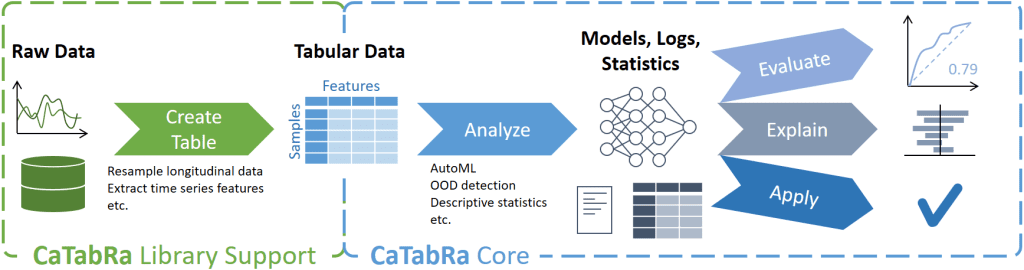

Ein wesentlicher Erfolgsfaktor für die Anwendung von Machine Learning in der Medizin ist das Vertrauen von Ärzt*innen und Patient*innen in die Datenbasis und die davon abgeleiteten Vorhersagemodelle. Grundlage für dieses Vertrauen sind Methoden zur Validierung der Daten, zur Interpretation der Modellvorhersagen und zur Analyse von Abweichungen. Durch die Bereitstellung und Nutzbarmachung dieser Methoden in einem Datenaufbereitungs- und Analyseframework, welches die vollständige Datenverarbeitungspipeline umfasst, unterstützt die Forschungsabteilung Medizin-Informatik die Mediziner*innen in der klinischen Praxis.

Die Erarbeitung der erforderlichen Strukturen zur Datenverarbeitung erfolgt im Rahmen von ausgewählten Beispielszenarien. Anwendungsbereiche sind etwa das Verlegungsmanagement auf der Intensivstation, die Optimierung des Manchester-Triage-Systems in der Notaufnahme, die optimale Applikation von Blutkonserven oder die Vorhersage kardialer Instabilität.

Im Fokus steht die Erforschung einer generischen und einfach konfigurierbaren Datenverarbeitungskette für bewährte und neueste Methoden, um auch zukünftigen Anforderungen gerecht zu werden. Neben strukturierten Daten dienen auch Bild-, Video- und Signaldaten sowie Kombinationen unterschiedlicher Datenmodalitäten und eine spezialisierte Merkmalsextraktion als Informations- und Datengrundlage.

Der Forschungsfokus liegt auf der interaktiven Datenanalyse unterschiedlicher Modalitäten mit Fokus auf Interpretierbarkeit und Rückverfolgbarkeit von Einzeldaten oder Datengruppen im Sinne von „Explainable AI“. Gerade in der Medizin ist die Transparenz für die Akzeptanz KI-basierter Software von besonders hoher Bedeutung.

CaTabRa ist ein Python-Package zur weitgehend automatisierten Analyse von tabellarischen Daten. Dies umfasst die Erstellung von deskriptiven Statistiken, die Erstellung von Out-of-Distribution-Detektoren, das Training von Vorhersagemodellen für Klassifizierungs- und Regressionsaufgaben und die Auswertung/Erklärung/Anwendung dieser Modelle auf ungesehene Daten.